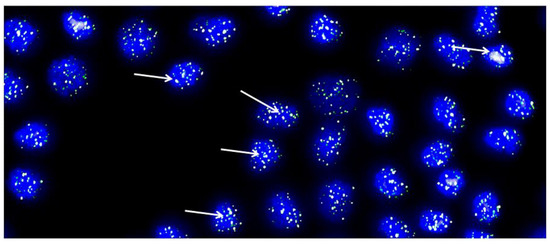

We studied cartilage biopsies from three patients with knee articular cartilage lesions that were going to undergo a HD-ACI. Biopsies were taken from a nonbearing area of the medial condyle and chondrocytes were isolated and cultured following the standard protocol established for HD-ACI. Briefly, cartilage biopsies suspended in Dulbecco’s Modified Eagle Medium (DMEM; Lonza Group Ltd., Basel, Switzerland) were processed in a sterile GMP (Good Manufacturing Practice) certified room, approved by the Spanish Health Authorities. Chondrocytes were isolated by digestion collagenase and cells were cultured in DMEM supplemented with 10% of autologous serum. When culture reached 80% confluence cells were detached and a maximum of three passages were performed until 40 to 50 million cells were obtained. After the third passage, a 1 million cells aliquot was reserved to be used for telomere length estimation, being the remaining cells implanted to patients. In each culture, the doubling time and the number of cells in each division were estimated by the trypan-blue exclusion method, assuming that cells grow exponentially. Telomere length was estimated by quantitative in situ fluorescent hybridization method (Q-FISH) in metaphasic cells [33].

A representative example of Q-FISH in metaphasic cultured chondrocytes is depicted in Figure 4. Nuclei are stained in blue and telomeres in white-greenish fluorescence (indicated by arrows). After three passages, cells were in culture for a mean time of 45.67 days (±9.45 days), being the mean doubling time of 4.53 days (±0.71 days). It has been published that chondrocytes can become senescent after 30–35 population doublings, calling this cut-off Hayflick’s limit [34]. In our studied samples, cells divided a mean of 10.04 times (±0.82 times), which is three-folds smaller than Hayflick’s limit. On the other hand, regarding telomere measurement, in the three examined samples, the 20th percentile of the telomere length was 6.84, 6.96, and 7.06 kbp, respectively, and the median telomere span was 10.30, 10.47, and 10.73. These results mean that in 20% of the chondrocyte population studied, telomere length was 6.84–7.06 kbp while in 50% of them, telomere span was 10.30–10.73 kbp, which are long enough to think that most population of cultured cells are not senescent. These results allowed us to conclude that cultured chondrocytes for implantation are not senescent, at least in terms of telomere length and number of cell divisions involved in the procedure carried-out to obtain the necessary number of cells for HD-ACI. Although the number of studied samples was very little (only three), the low variation coefficients estimated from the telomere length measurement (3.54–3.94), made us affirm that our results are consistent enough to extrapolate to all chondrocyte cultures under our conditions.

Figure 4. Representative metaphase image from chondrocytes cultured from each cartilage biopsy. The image showcases DAPI-stained nuclei in blue, while the telomeres are visualized as green/white fluorescent signals. The images were captured with the Leica Q-FISH software, using a linear acquisition mode and an integration time of 400 ms to avoid oversaturation of fluorescence intensity. The recordings were made with a COHU CCD camera on a Leica Leitz DMRB fluorescence microscope. Several arrows have been added to indicate the location of some telomeres as an example [32].